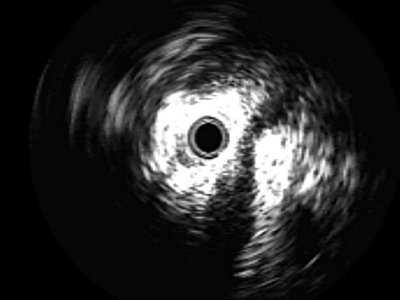

При интрауретеральном эхосканировании в неизмененной части мочеточника четко визуализируются пониженной эхогенности мышечный слой, вокруг гиперэхогенная адвентиция. Толщина стенки мочеточника колебалась в пределах 0,7-1,2 мм. Вокруг его стенки определяется повышенной эхо генности парауретеральная клетчатка (рис. 7).

Рис. 7. Эхограмма нормального мочеточника и парауретеральных тканей:

1 - стенка мочеточника; стрелка - адвентиция.